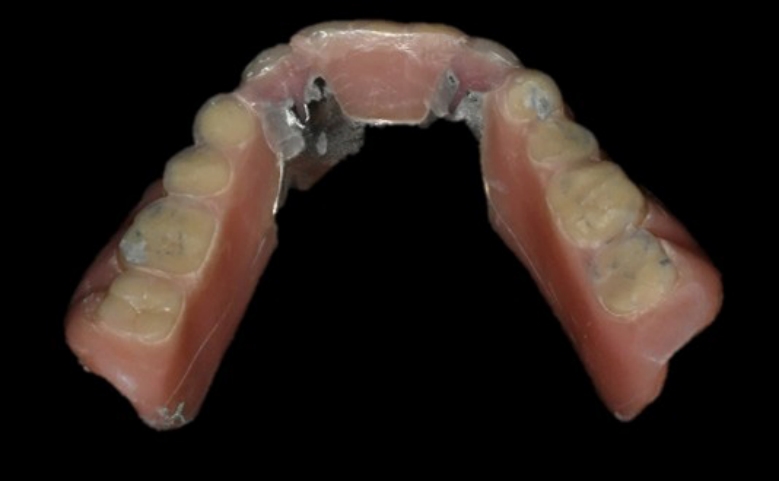

Fig. 14.

The final prosthesis is functionally and esthetically fitted with the patient. A. Right side view. B. Frontal view. C. Left side view.